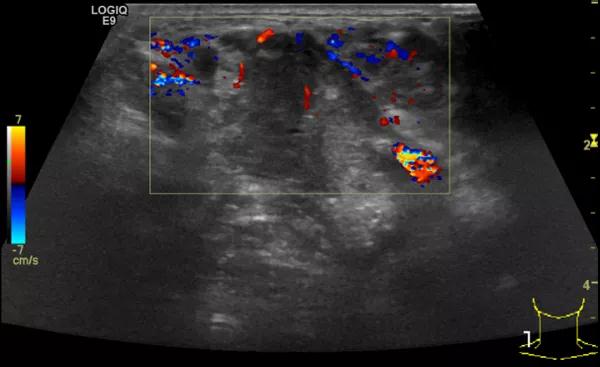

随后,徐栋教授进一步分享了五个临床实战病例,带来了更直观的热消融治疗经验。第一个病例是62岁肺癌患者,术后1年余发现双侧锁骨上淋巴结复发,侵犯神经,存在静脉回流、淋巴回流障碍,肿胀、疼痛非常明显。影像显示患者淋巴结边界不清、形态不规则,存在浸润,血流强化增强。由于患者在系统治疗后进展,且主要目的缓解症状、减瘤。局麻下行热消融术,从后向前逐层消融,热消融之后超声造影即刻评估显示完全充盈缺损,完全覆盖病灶。

(病例1图例)